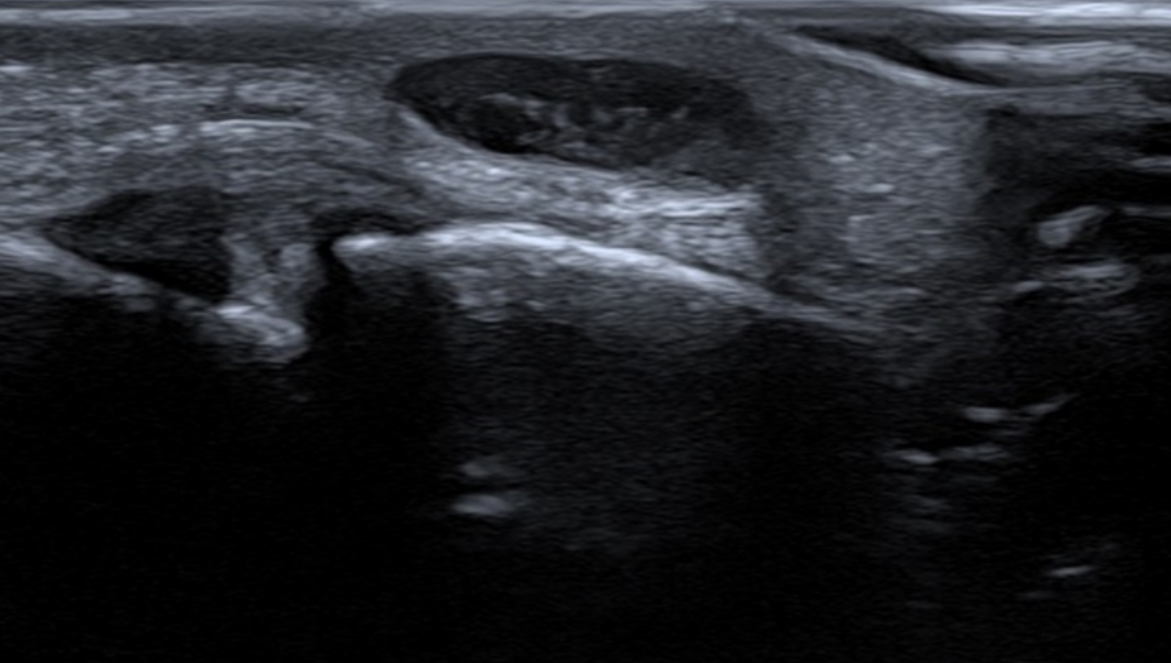

The palpable nodule along the radial aspect adjacent to the PIPJ of the left middle finger corresponded to an oval shaped subcutaneous lesion which contained internal echoes and on first inspection appears solid (fig.1). However, on turning on color doppler, there was clear movement of the internal echoes within this lesion suggesting that it was cystic with proteinaceous material rather than being solid. This changed the differential diagnosis significantly. In addition, there was no definite connection with the PIPJ but appeared to abut the tendon sheath.

The appearances, particularly with the Doppler findings, confirmed that this was a ganglion cyst with proteinaceous material.

Ganglionic cysts with thick proteinaceous material however can mimic the ultrasound appearance of solid masses and be mistaken for tumors. In this case, Doppler was crucial for the diagnosis where at first glance, the lesion appears solid on B mode. However, the acoustic streaming effect of colour/power Doppler confirmed the cystic nature of this lesion, which cannot be induced in solid lesions. Acoustic streaming is the utilization of Doppler technique, whereby absorption of high amplitude acoustic oscillations results in the continuous flow of fluid. This explains why we can observe the movement of the proteinaceous material within the ganglion cyst (fig. 2). This simple, yet very effective application of Doppler can help avoid a further MRI or invasive biopsy.